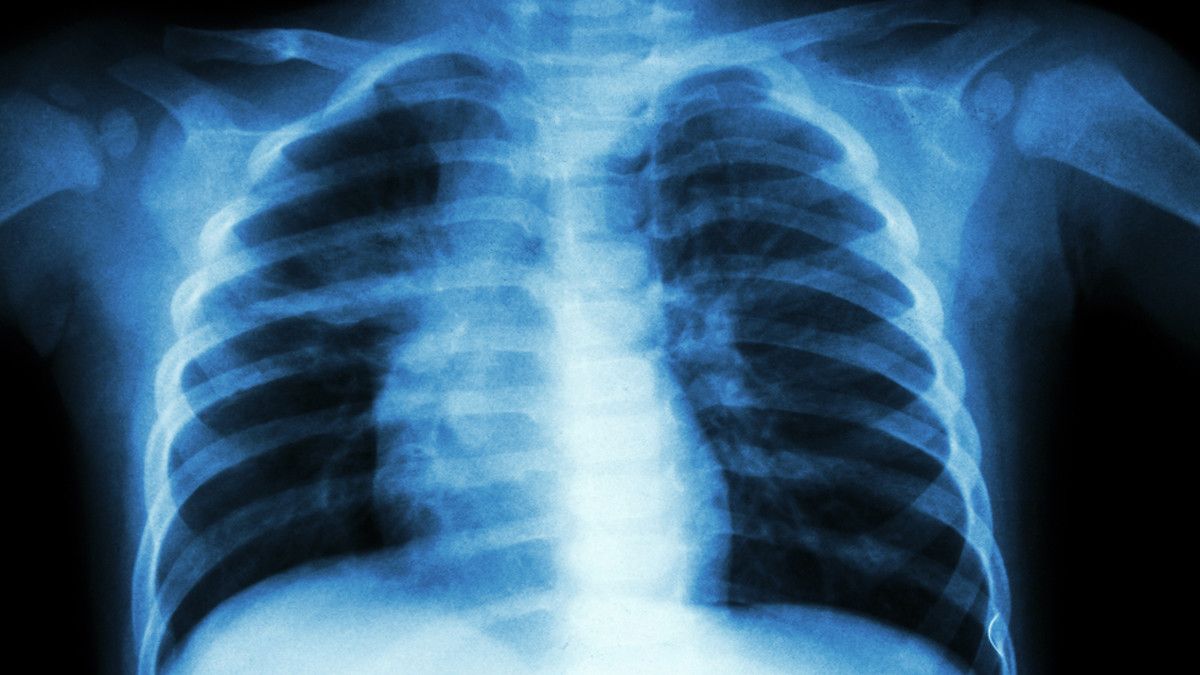

Pneumonia atau lebih dikenal dengan istilah paru-paru basah merupakan sebuah penyakit peradangan yang menyerang jaringan paru. Kondisi ini menyebabkan kantung udara di paru terisi cairan, sehingga organ tersebut tidak bisa bekerja dengan maksimal.

Mengerikannya, pneumonia tidak hanya menyerang orang dewasa, tapi juga anak-anak. Bahkan, anak yang mengalami penyakit ini berisiko tinggi terkena komplikasi, khususnya jika penyakit tidak segera diatasi dengan cara yang tepat. Waspada, komplikasi pneumonia pada anak bisa sebabkan kematian!

Menurut dr. Devia Irine Putri, pneumonia dapat disebabkan oleh infeksi bakteri, virus, jamur, maupun parasit pada paru-paru. Di antara semua mikroorganisme tersebut, infeksi bakteri dan virus adalah penyebab pneumonia yang paling sering ditemukan.

Selain itu, pneumonia juga bisa terjadi akibat adanya zat atau cairan yang masuk ke dalam paru-paru. Kondisi ini disebut dengan pneumonia aspirasi, dan membuat penderitanya sering tersedak.